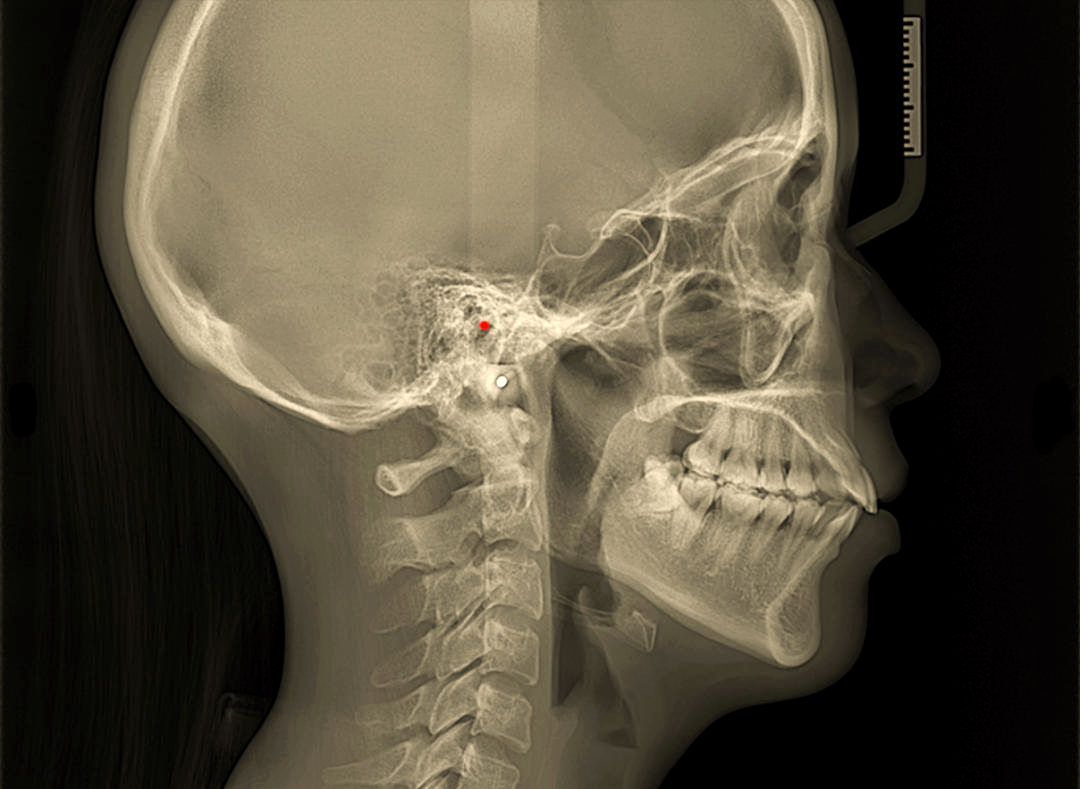

头影测量中的关键平面:你的面孔密码 🔍

正畸前的秘密:头影测量为何如此重要